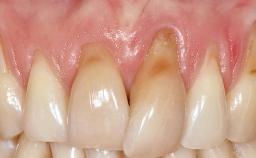

A 30-year-old woman was referred by her general dentist for evaluation of an esthetic complication related to previous implant treatment for congenitally missing maxillary lateral incisors. The patient’s chief complaint was the inadequate esthetic appearance of her smile. The case demonstrates the use of a combined approach to achieve optimal results. Two different flap designs - a tunnel technique and a coronally advanced flap - are employed based on the surgical objectives for the affected site.

Soft Tissue Grafting Yes

Soft Tissue Contour and Volume Slightly compromised